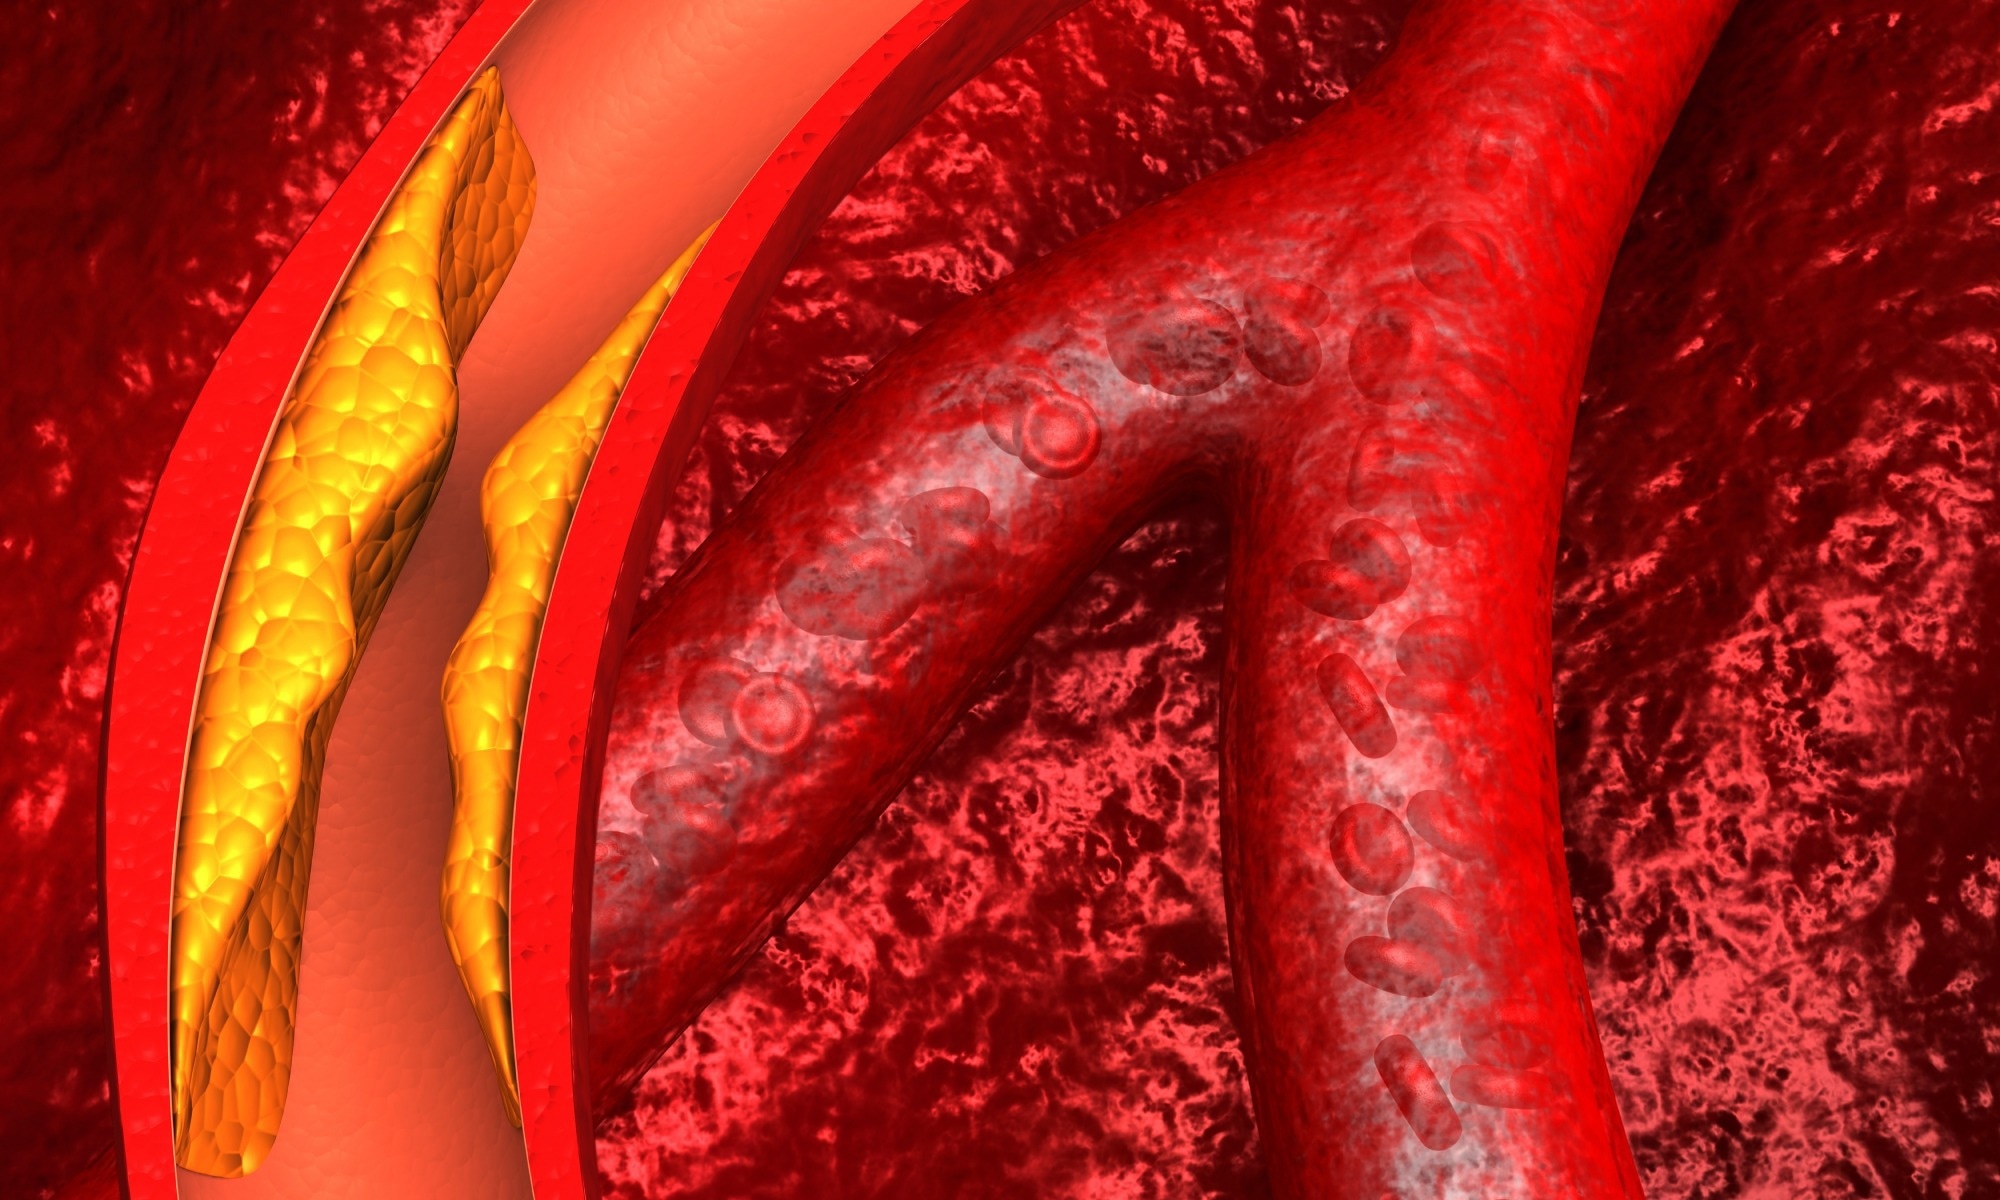

Study: Safety and Efficacy of Obicetrapib in Patients at High Cardiovascular Risk. Image Credit: Explode / Shutterstock

Study: Safety and Efficacy of Obicetrapib in Patients at High Cardiovascular Risk. Image Credit: Explode / Shutterstock